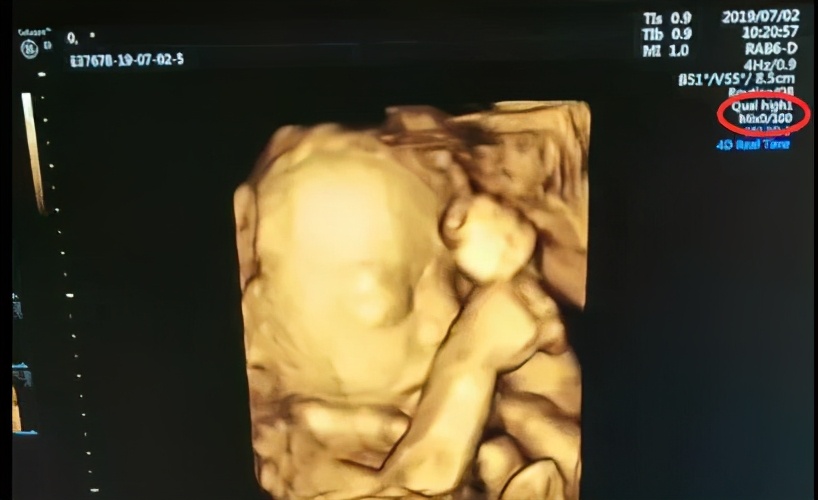

四维胎儿图片,四维图片胎儿全图

四维图片胎儿全图

胎儿四维照片

四维彩超图片

胎儿四维

四维图片

胎儿四维照片真实

四维彩超照片